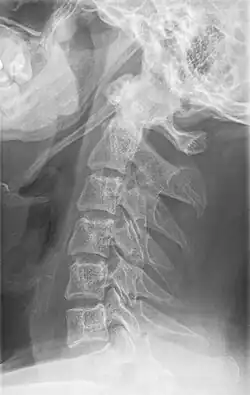

-

Radiograph, lateral view showing elongated stylohyoid process and stylohyoid ligament ossification -

Radiograph, lateral view showing joint-like formation in ossified stylohyoid ligament -

Imaging is important and is diagnostic. Visualizing the styloid process on a CT scan with 3D reconstruction is the suggested imaging technique.[13] The enlarged styloid may be visible on an orthopantogram or a lateral soft tissue X ray of the neck.